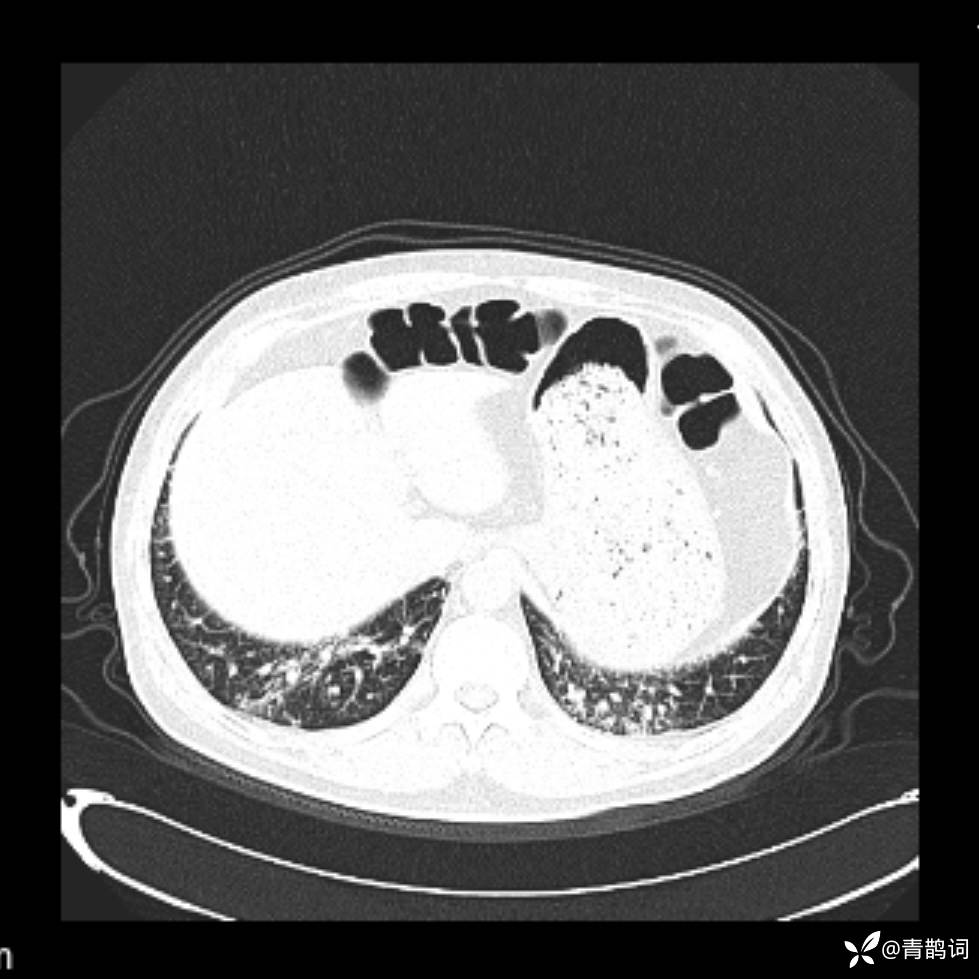

患者年龄:30岁。

患者性别:男。

简要病史:左颜面部肿胀2年,反复咳嗽咳痰,逐渐加重。

结合病史及影像学表现,期待评论区各位老师各抒己见~